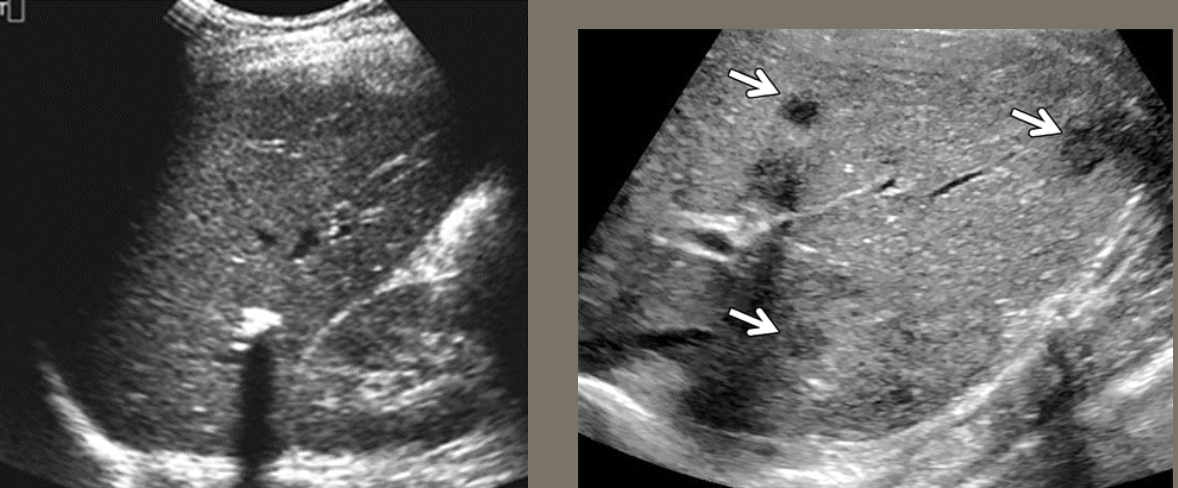

Metastatic Disease (METS) → most common form of neoplastic involvement of the liver

clinical hx: active CA diagnosis or prior remission history

s/sx: can be asymptomatic, abnormal LFTs, jaundice, poor appetite, abdominal distention/bloating & weight loss

2D US: single or multiple solid lesions, varying sizes, can have bullseye appearance, echogenic, or hypoechoic, enlarged liver, can cause pseudo nodularity

color doppler: hypo to hypervascular